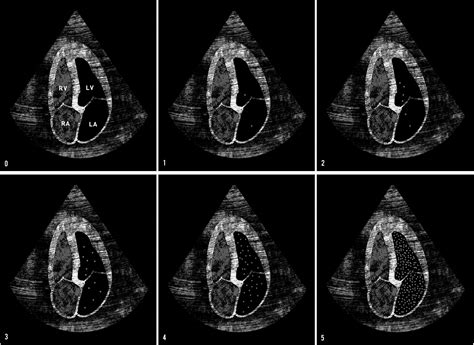

• Bubble Appearance: The appearance and movement of the bubbles can indicate the presence of shunts or other structural issues.

• Timing: The timing of the bubble appearance in different heart chambers can help pinpoint the location of the abnormality.

• Quantification: The number of bubbles and their distribution can provide quantitative information about the severity of the condition.

Based on these observations, the cardiologist will make a diagnosis and recommend appropriate treatment options.